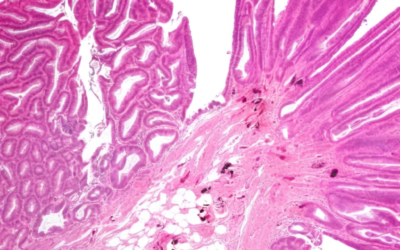

New Research Reveals Critical Differences in Cancer Risk from IBD-Related Precancerous Lesions

If you’re living with inflammatory bowel disease, the possibility of developing colorectal cancer has likely crossed your mind during quiet moments between…